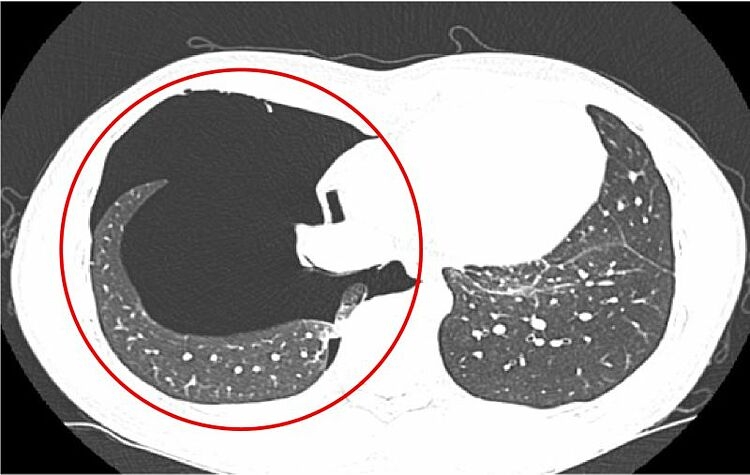

Kết quả chụp X-quang và CT ngực ghi nhận hình ảnh tràn khí khoang màng phổi phải kèm theo tổn thương nhu mô phổi (đám đông đặc ở thùy trên và phân thùy S5 phổi phải). Bác sĩ nhận định tình trạng này do chấn thương phổi trong lúc gắng sức.